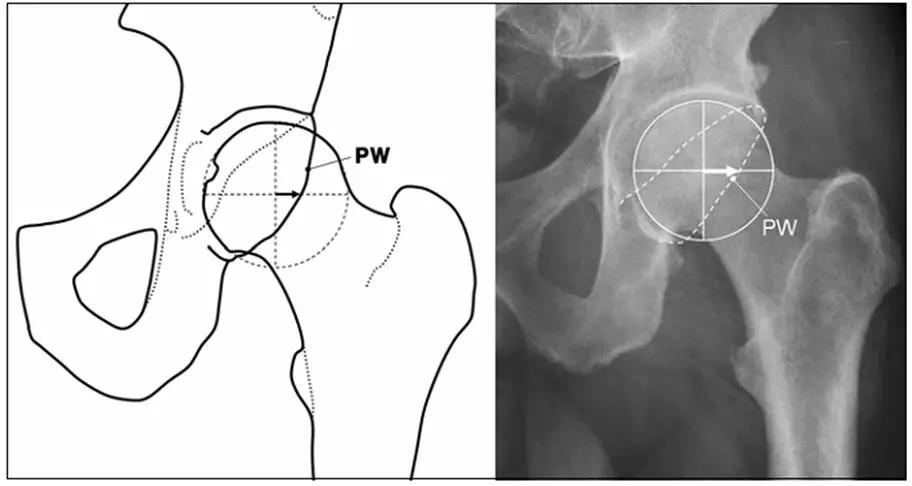

- 股骨头中心O点为圆心,股骨头正常最大半径为r,从股骨头颈连接处骨质与这个圆的交点(A点)到股骨头中心点作直线OA,此直线与股骨颈中轴线OB的交角为α角。

- 反映股骨颈骨赘突出程度,α角越大,越容易发生前上方股骨头颈与髋臼唇的撞击。

- FAI组中该角平均为74.0°±5.4°,正常对照组为42.0°±2.2°。

- α角>50°是诊断FAI的临界值。